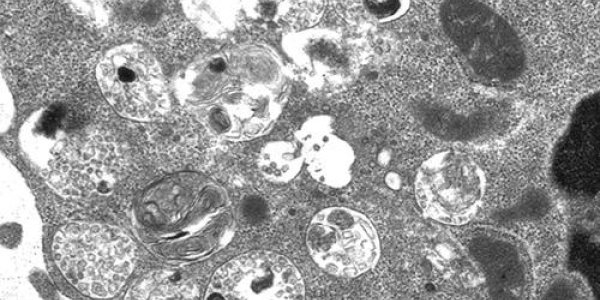

A group of white blood cells known as B cells play a key role in the human immune response but need a protein-targeting signal called mannose 6-phosphate (M6P) in order to proliferate, differentiate…